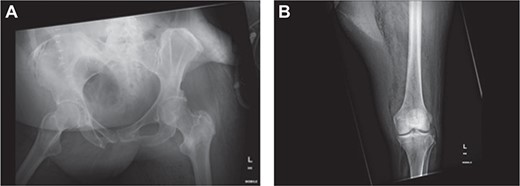

X-ray of (a) pelvis and (b) left lower limb demonstrated obvious air in soft tissue compartment in right gluteal and left thigh.

Within 14 hours postoperatively, she developed an erythematous patch on her left thigh, and a creatine kinase of 19 000. A bedside finger test was performed which showed dirty dishwater fluid, necrotic fat and lack of bleeding. She was taken to theatre for urgent debridement for suspected NF. Antibiotics were changed to Meropenem, Vancomycin, Lincomycin and Fluconazole. She had extensive debridement of the soft tissue circumferentially on the left thigh, including some muscle. In 10 hours postdebridement, there was a radiological evidence of disease progression with gas in muscle compartments on the lower limb X-rays (Fig. 2a and b), and CT abdomen and lower limbs demonstrating gas throughout the whole left leg and a non-contiguous area in the right gluteal region (Fig. 3a and b). A diagnosis of multi-focal non-contiguous necrotising myositis was made.